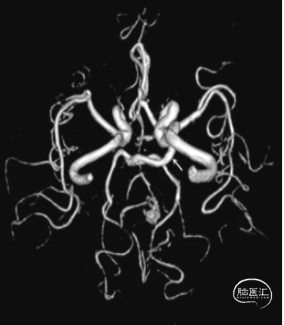

3. L-ICA(三维重建):(图3)

图3

2. 3D重建:L-P2段动脉瘤,瘤体:3.9mm*4.5mm,瘤颈:3.9mm。L-PCA-P2段瘤体近端局限性狭窄,狭窄率约60%,左侧颈内动脉C6段小动脉瘤:1mm*1.5mm,瘤体向下。(图8)

图8